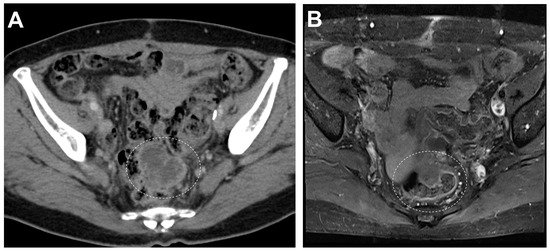

Representative gross findings of the ovary. The left ovary, fragmented, was totally replaced by a tumor obscuring the normal tissue, measuring 18.7 × 15.0 × 3.0 cm (A). The tumor involved the ovarian surface with capsular rupture. The mass was heterogeneous and consisted of portions showing multiloculated cysts with internal hemorrhage (yellow dashed line) and a solid area with papillary configuration (white dashed line). The solid area, measuring 5.3 × 4.0 × 3.5 cm, was white-grayish and relatively friable. Due to the fragmentation of the specimen, it was difficult to match the MRI findings exactly, but the solid papillary area (white dashed line) was presumed to be the solid component portion observed on the cranial side (A). The cut surface of the solid component was mostly ill-defined, yellow-to-tan, and firm without necrosis (B).

Pathological examination revealed a collision tumor with ovarian capsular rupture and uterine serosal implants of a mesonephric-like adenocarcinoma (MLA) component (0.4 × 0.3 cm). The bilateral fallopian tubes and omentum were not involved in the tumor, and there was no lymph node metastasis. The patient was diagnosed with FIGO stage IIA and treated with adjuvant chemotherapy.